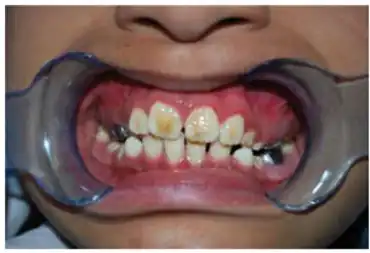

There are some physical symptoms that have been associated with KTS. The most prominent symptom is amelogenesis imperfecta which gives the teeth a stained brown-yellow color. The enamel is thin, rough, and prone to crumbling. Two types of amelogenesis imperfecta (AI) have been seen in KTS patients. The first is Hypoplastic which is caused by the enamel being underdeveloped, and the second is hypo-calcified which causes the enamel to be soft and chalky. AI originated as a heterogeneous syndrome but has been observed as homogeneous in the case of KTS.[5][6][10] Other physical symptoms that some cases have presented with include broad thumbs and toes, microcephaly, coarse hair, mildly asymmetric skull, up slanting palpebral fissures which is where the outside corners of the eyes are higher than normal, and smooth philtrum which is where the upper lip does not have a dip in the center.[5][10]

Diagnosis occurs based on the two most common features of this syndrome: epilepsy and symmetrical enamel hypoplasia also known as Amelogenesis Imperfecta. Because the tooth discoloration caused by amelogenesis imperfecta is often thought to be caused by environmental factors or other diseases, diagnosis of this syndrome is sometimes overlooked. The onset of symptoms can occur when the patient is between one month and four years old, contributing to the misconception that tooth discoloration is due to the environment.[2][7][14]